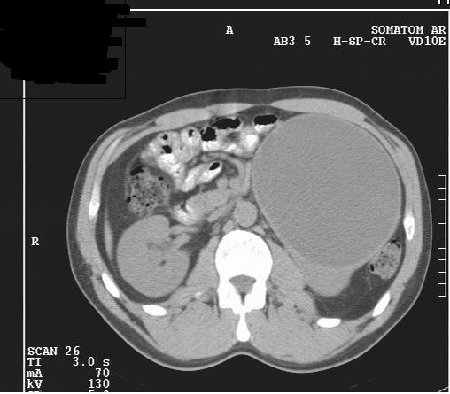

М. 37 лет, жалоб нет, амб. приём, причина назначения УЗИ ОБП: СОЭ 42мм

б\б и м\э консист., как говорится.   Исходит из н\ полюса левой почки